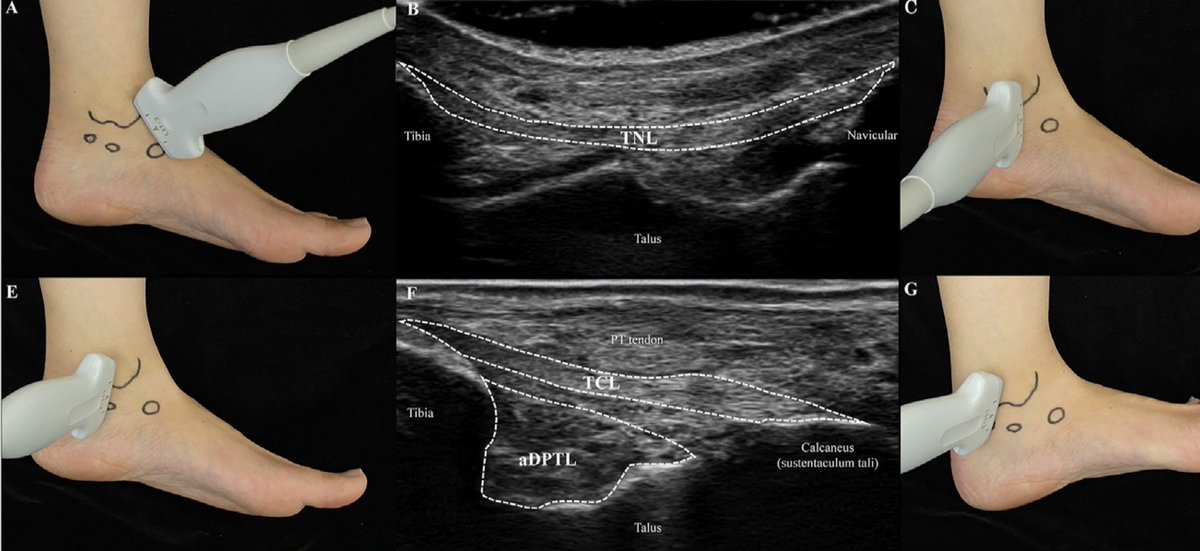

🤔 Repensando el 'Síndrome' del Seno del Tarso: ¿Es realmente un conjunto único de síntomas o varias patologías distintas? Sumérgete en la discusión y descubre por qué la precisión en el diagnóstico es clave. #pieytobillo #ortopedia #traumatología aware.doctor/blog/sindrome-…